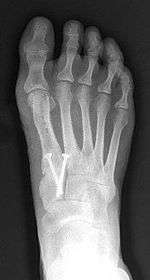

Syndesmosis procedure addresses specifically the two fundamental problems of metatarsus primus varus deformity that gives rise to the bunion deformity. They are leaning and instability of the first metatarsal bone . Syndesmosis procedure uprights the leaning first metatarsal bone with strong binding sutures between it and the second metatarsal bone (Fig. 2) and then also stabilizes it uniquely by creating a fibrous connecting bridge between these two bones (Fig. 3,4). First metatarsal bone can be readily realigned is because by definition of the metatarsus primus varus deformity its first metatarsal is abnormally loose and mobile.